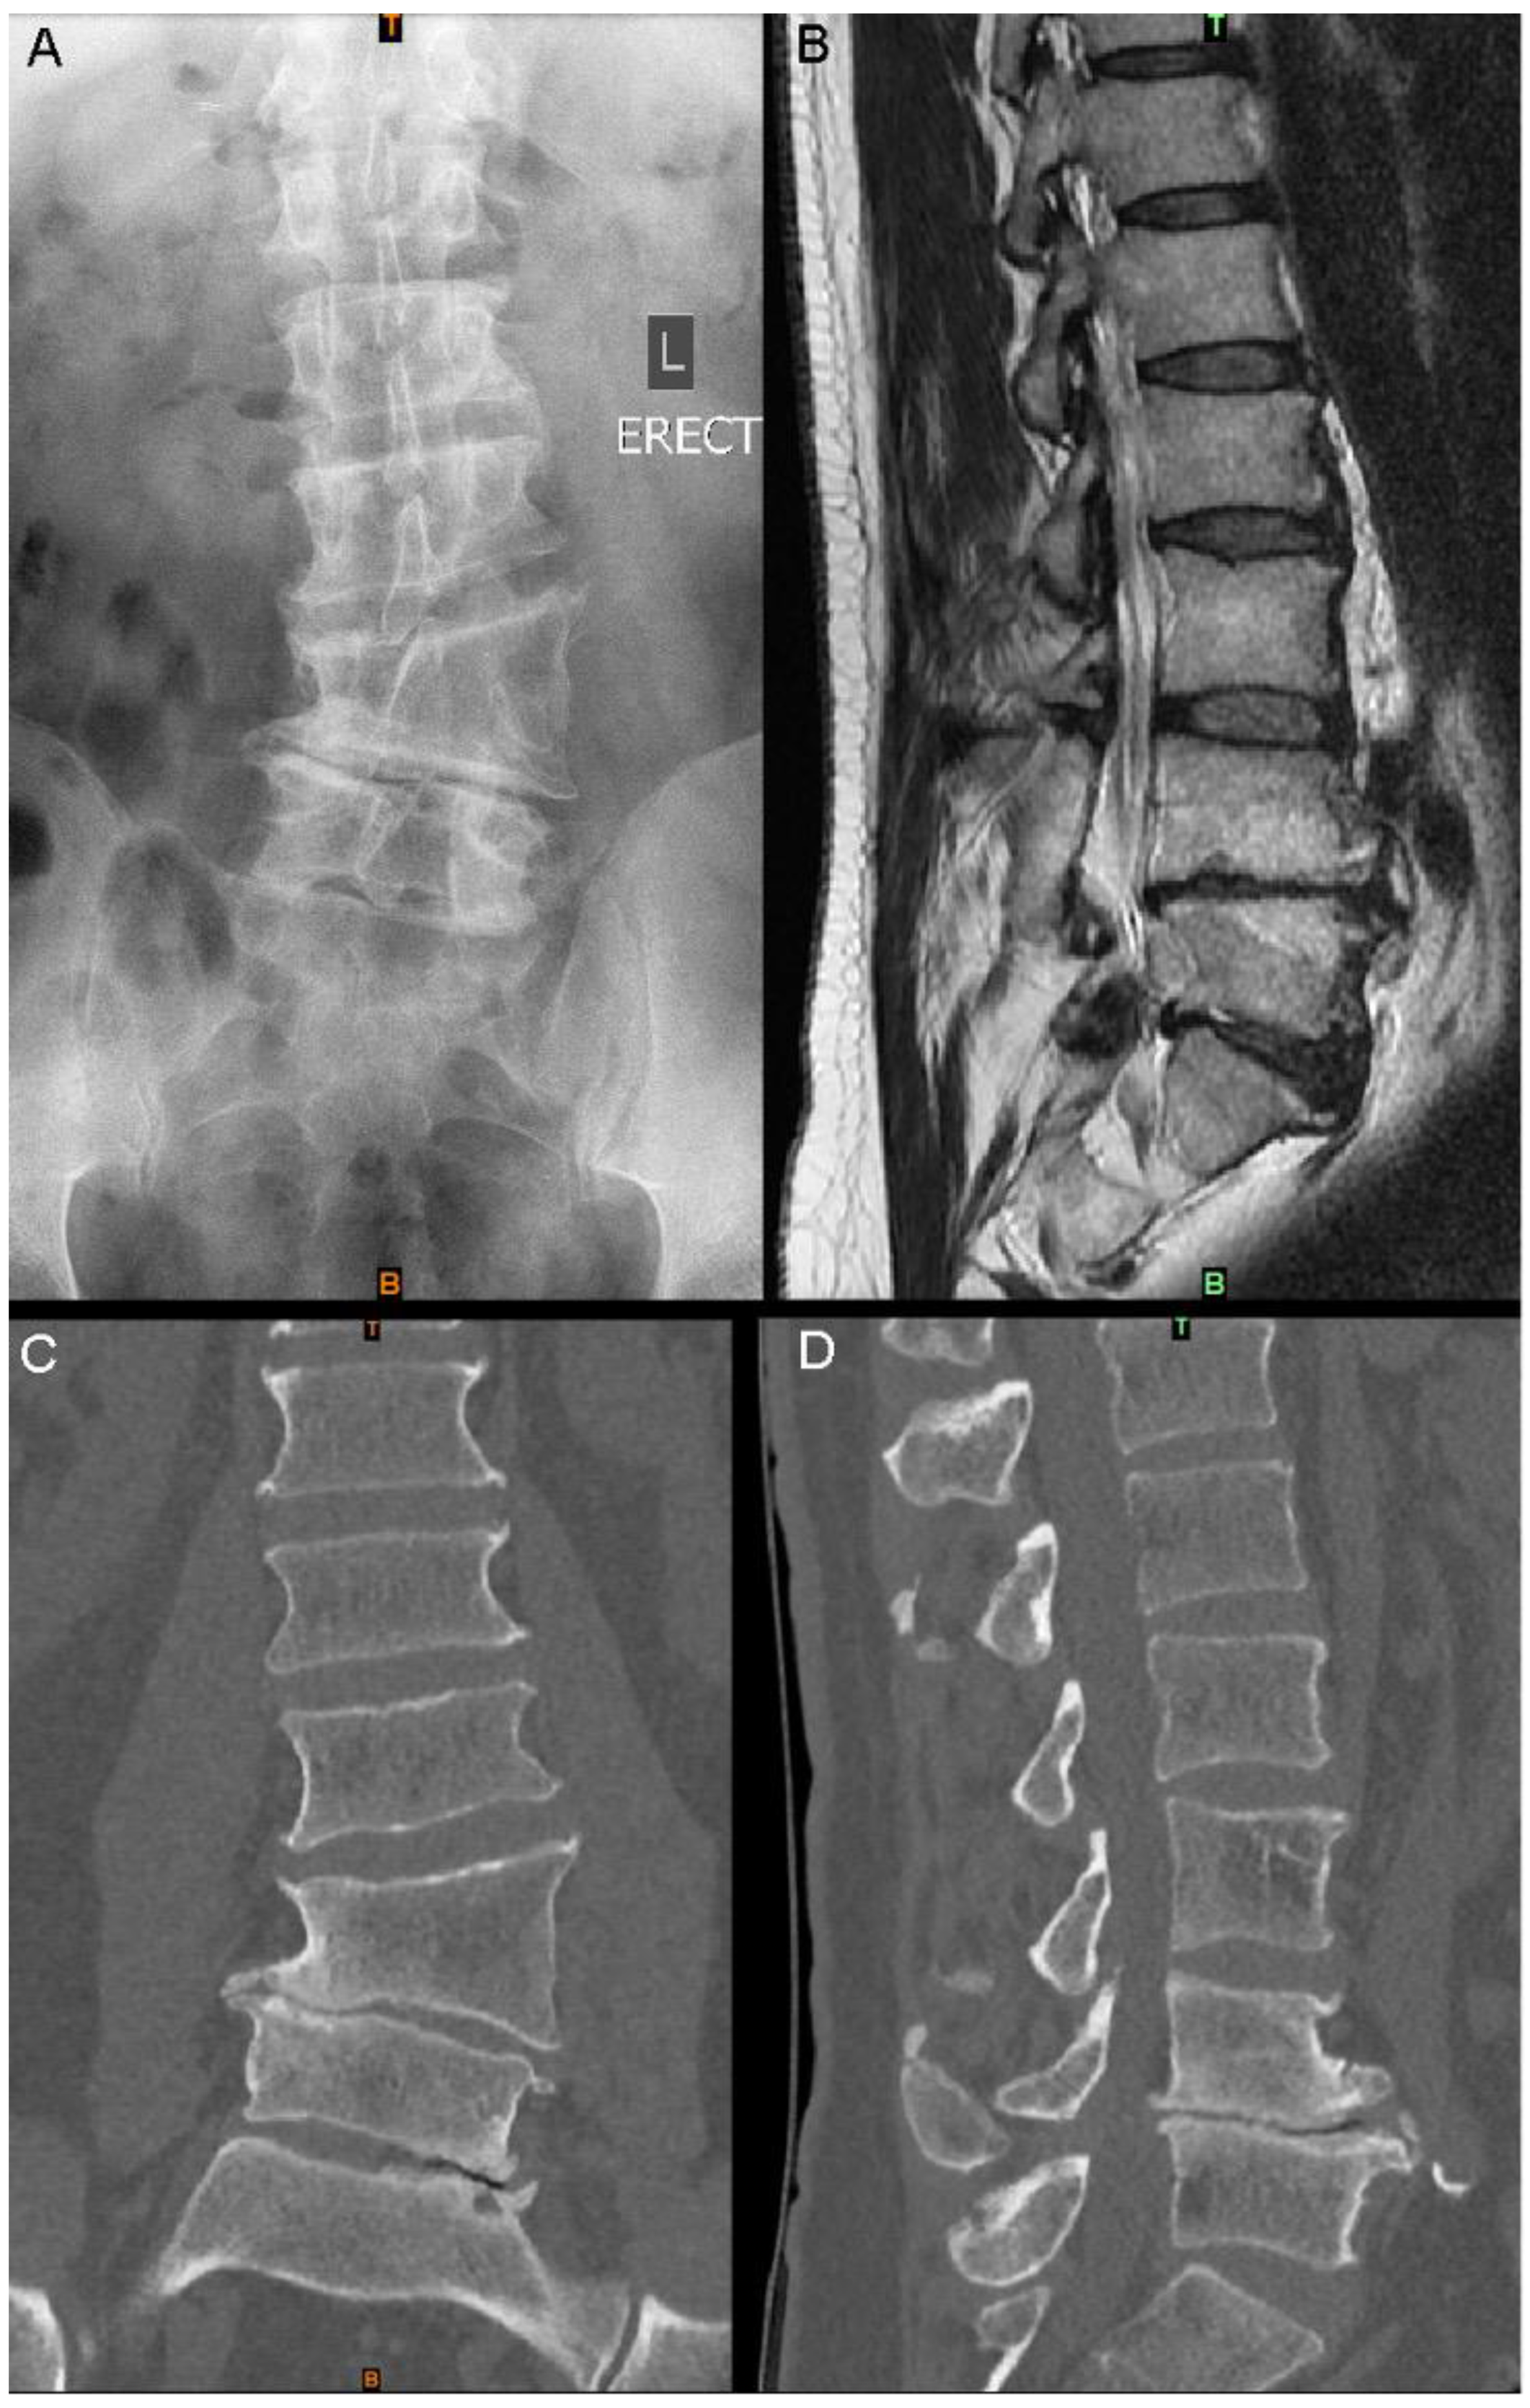

A 53-year-old man presented with a 12-month history of severe, progressive back and bilateral leg pain (visual analogue scale (VAS) pain score of 8/10). No deficits in sensory or motor deficits were present on examination; however, the patient reported difficulty in performing occupational tasks. The patient reported a background of chronic lower-back pain since childhood, secondary to an L4 lateral hemivertebra diagnosed in adolescence. Conservative management had successfully provided symptomatic relief until the recent onset of leg pain. CT imaging demonstrated the long-standing L4 hemivertebra and mild congenital scoliosis, as well as associated degenerative changes at the L4/5 and L5/S1 levels, including a loss of disc and neuroforaminal heights, and extensive osteophytosis (Figure 1 and Figure 2).

Figure 1.

Imaging at presentation: (A) standing AP X-ray; (B) sagittal slice of T2 MRI of the lumbar spine; (C) lumbar spine CT coronal slice; (D) lumbar spine CT sagittal slice at a similar position to (B).